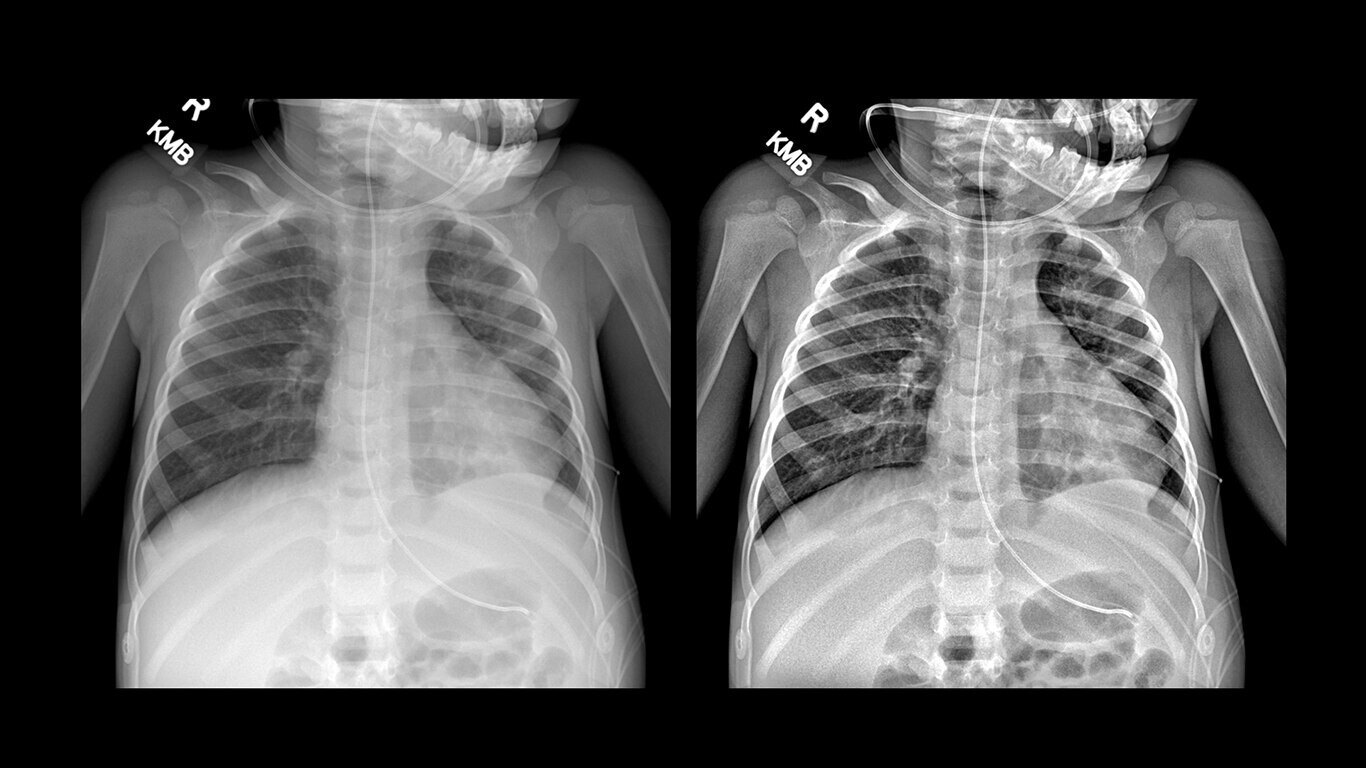

Uncompromised image quality

Capture high-resolution images with powerful, glassless detectors that weigh 40% less than previous generations3